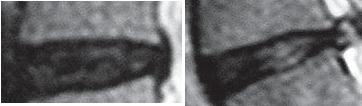

На МРТ № 128 наблюдается состояние поясничного отдела позвоночника после операции: рецидив грыжи межпозвонкового диска в сегменте LV-Sr с отрывом секвестра и его миграции в краниально-дорсальном направлении, разрыв задней продольной связки. На МРТ № 129 наблюдается состояние поясничного отдела позвоночника после лечения методом вертеброревитологии: отсутствие грыжи межпозвонкового диска в сегменте L — S. В межпозвонковых дисках в сегментах LIV-LV, L — SI наблюдается процесс репаративной регенерации. ![]() На МРТ № 130 наблюдается состояние поясничного отдела позвоночника после двух хирургических операций: рецидив грыжи межпозвонкового диска в сегменте LV-SI. На МРТ № 131 наблюдается состояние поясничного отдела позвоночника после лечения методом вертеброревитологии. Рецидив грыжи межпозвонкового диска после двух хирургических операций — и это у молодого человека в возрасте 16 лет! Чрезмерное увлечение компьютером, малоподвижный образ жизни основательно подорвали его здоровье. Всё это привело к тому, что в течение года, начиная с пятнадцатилетнего возраста, он практически не выходил из больниц. После первой хирургической операции на позвоночнике, менее чем через месяц, боли возобновились. Спустя два месяца его вновь прооперировали по поводу рецидива — грыжи межпозвонкового диска. После второй хирургической операции боли наблюдались практически два месяца подряд, потом затихли, но полностью так и не прошли. Через пять месяцев появилась слабость в обеих ногах. Сделали снимки МРТ, диагностировали рецидив грыжи межпозвонкового диска, естественно рекомендовали сделать очередную третью хирургическую операцию. В промежутках между операциями молодой пациент несколько раз находился на стационарном лечении в неврологическом отделении городской больницы. Именно там, после того как у парня была диагностирована очередная грыжа, лечащий врач посоветовал не спешить с третьей операцией и порекомендовал ему обратиться ко мне в клинику. Конечно, этот случай был далеко не простым и пришлось основательно потрудиться как мне, так и самому пациенту над восстановлением его здоровья. Но зато результат порадовал всех тех, кто непосредственно участвовал в этом процессе, и кто косвенно ему способствовал. Можно сказать, ещё одна судьба была изменена и молодой человек спасён от инвалидной коляски. МРТ № 132МРТ № 133 ![]() На МРТ № 132 и МРТ № 133 — увеличенные фрагменты МРТ № 130 межпозвонковых дисков в сегментах LIV-LV и LV—SI до лечения методом вертеброревитологии. Структура межпозвонковых дисков неоднородна. ![]() На МРТ № 134 и МРТ № 135 — увеличенные фрагменты МРТ № 131 межпозвонковых дисков в сегментах LIV-LV и LV—SI, после лечения методом вертеброревитологии. Наблюдается весьма интересное явление — репаративная регенерация. Обратите внимание, насколько уменьшилось количество некрозной (мёртвой) ткани и увеличилось функциональной (живой) ткани. Примечательно, что хондроциты при регенерации в данной фазе формируют вертикальные и наклонные «колонны» согласно вектору нагрузки на межпозвонковый диск в районе фиброзного кольца. В центре межпозвонкового диска наблюдается не менее интересное явление — начало регенерации пульпозного ядра! Следующий случай можно назвать абсолютно беспрецедентным в истории науки вертебрологии и новым этапом в развитии вертеброревитологии. С помощью метода вертеброревитологии удалось практически полностью восстановить (по сути заново вырастить) отсутствующий межпозвонковый диск! И это без всяких химических препаратов, а исключительно благодаря естественному восстановлению биомеханики позвоночника — выстраиванию определённой биомеханической конструкции. При построении последней были достигнуты оптимальные условия для активизации резервных возможностей организма, что, в свою очередь, способствовало запуску репаративной регенерации вплоть до реституции диска, который в своё время был практически полностью удалён. Это удивительное явление, сравнимое разве что с реанимацией. Впрочем, всё по порядку. |